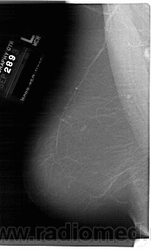

Жирная (не плотная) грудь

Умеренно плотная грудь

Плотная грудь

Маммограммы представляют собой изображения структур, проецируемых на плоскость: плотная грудная маммограмма, следовательно, состоит из многих других структур, которые необходимо проанализировать, чем более жирная, пустая грудь. По этой причине диагностировать рак молочной железы труднее для моложе, чем для пожилых женщин.

Нажмите на миниатюрные картинки, чтобы получить увеличенный размер.